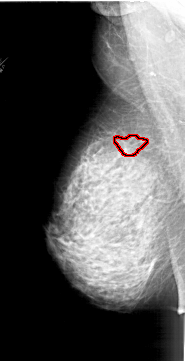

A_1878_1.LEFT_CC

LEFT_CC LINES 6871 PIXELS_PER_LINE 3286 BITS_PER_PIXEL 12 RESOLUTION 43.5 OVERLAY

FILE: A_1878_1.LEFT_CC.OVERLAY

TOTAL_ABNORMALITIES 1

ABNORMALITY 1

LESION_TYPE MASS SHAPE IRREGULAR MARGINS SPICULATED

ASSESSMENT 4

SUBTLETY 1

PATHOLOGY BENIGN

TOTAL_OUTLINES 2

BOUNDARY

CORE